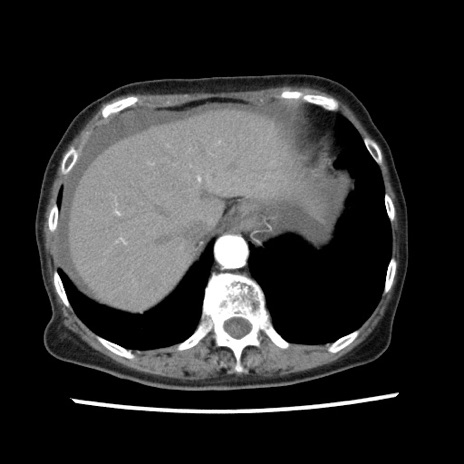

【症例】80歳代女性

【主訴】腹痛

【現病歴】8時間前から腹痛あり来院。

【既往歴】糖尿病、脂質異常症、子宮体癌にて子宮全摘術

【身体所見】意識清明・会話良好だが腹痛で苦悶様、全腹部にわたって反跳痛と圧痛あり

【データ】WBC 13600、CRP 0.14、LDH 224、CK 90